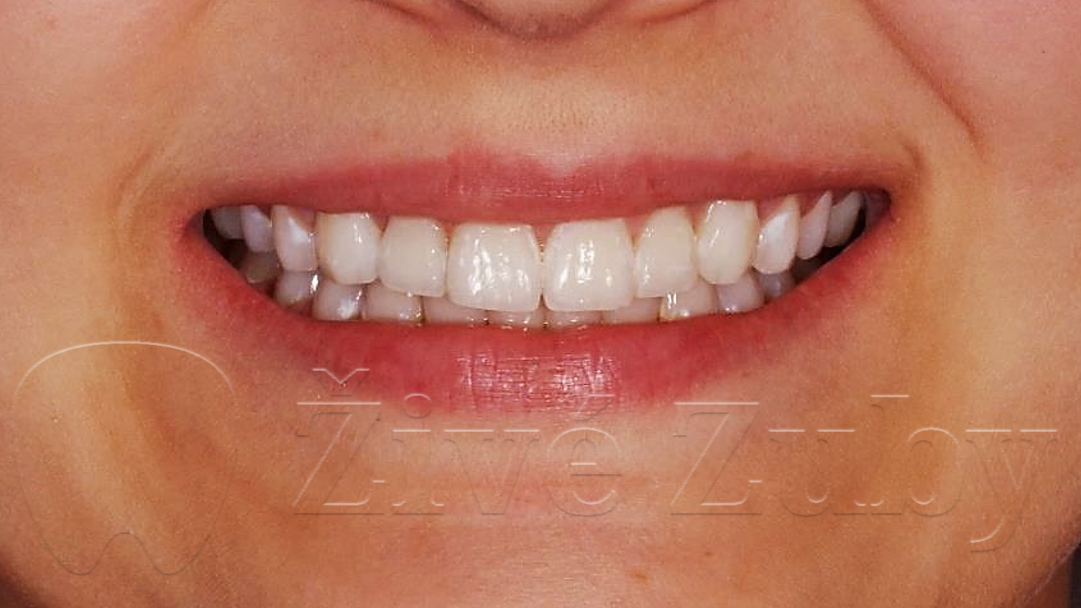

Mikroabraze a Infiltrace skloviny

(Ošetření Fluorózy a podobných lézí, demineralizaci skloviny, …)

Výchozí stav  ——- Kontrola po 2 letech